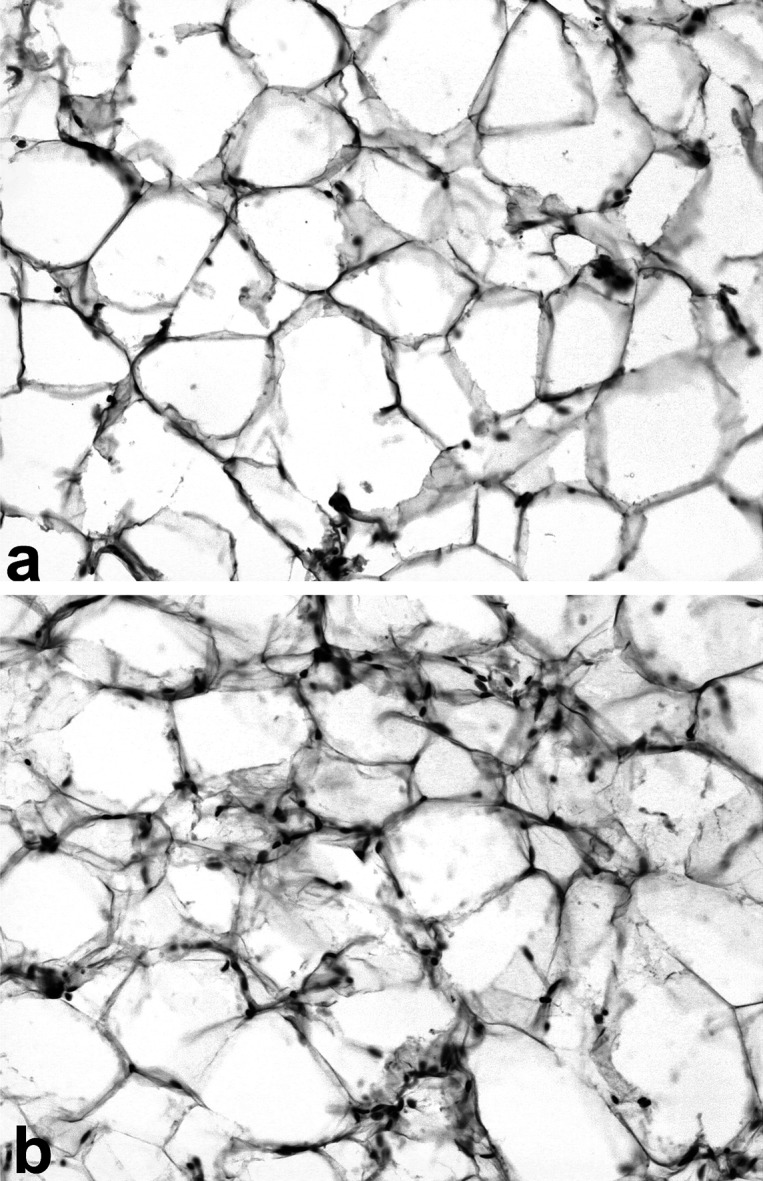

Adipose tissue morphology

The histological evaluation of adipose tissue revealed lymphoid infiltration of parametrium in all experimental groups. It is important to mention that the intensity of lymphoid infiltration revealed practically no difference between research groups. The most representative control and experimental slices of adipose tissue are shown in Figure 1.

Figure 1.

Histology of rat adipose tissue. Hematoxylin and eosin stains (×200). (a) adipose tissue of control rat. Only single lymphoid cells are present; (b) adipose tissue of rats obtaining FeSO4·12H2O and CuSO4 in respective concentrations of 3 and 4.88 mg/l. Lymphoid infiltration of adipose tissue is observed.